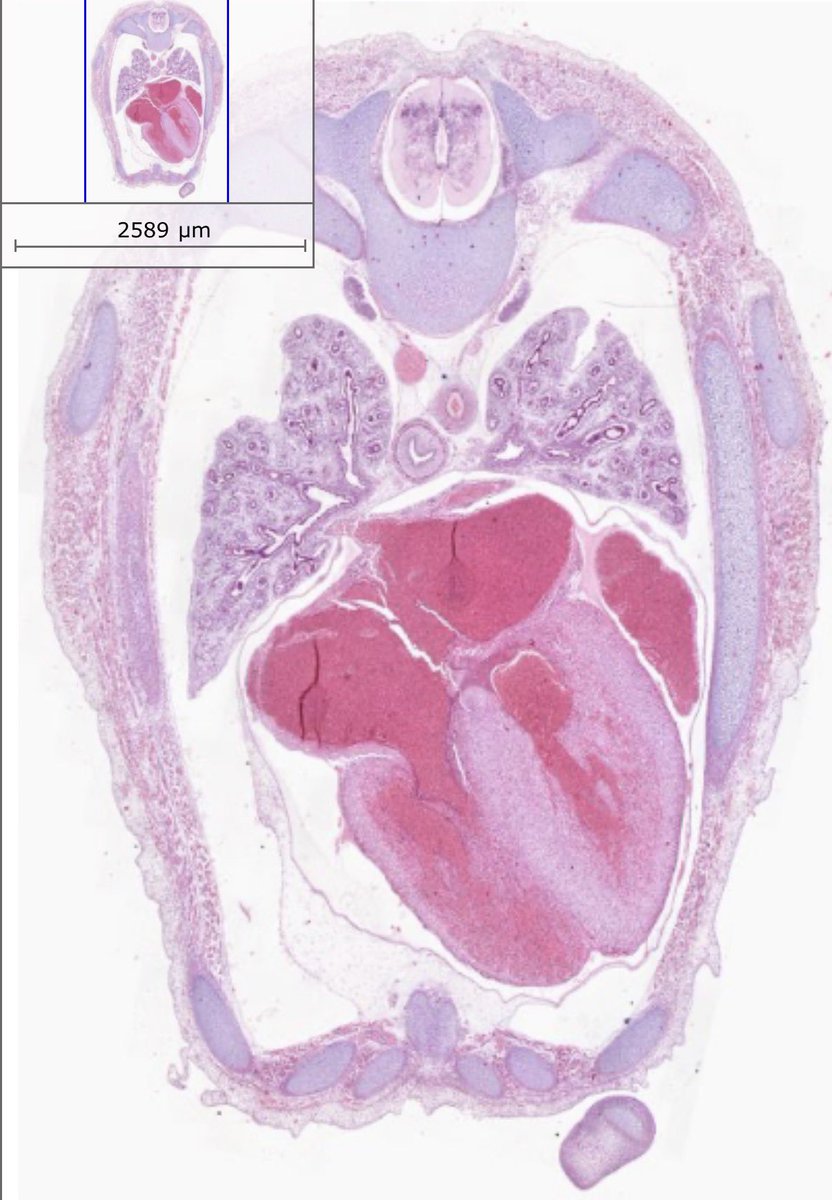

Microscopio Virtual - Histología y Embriología @histoemb , Facultad de Medicina, Universidad de la República, Uruguay. Desarrollado por @ernestomiquel